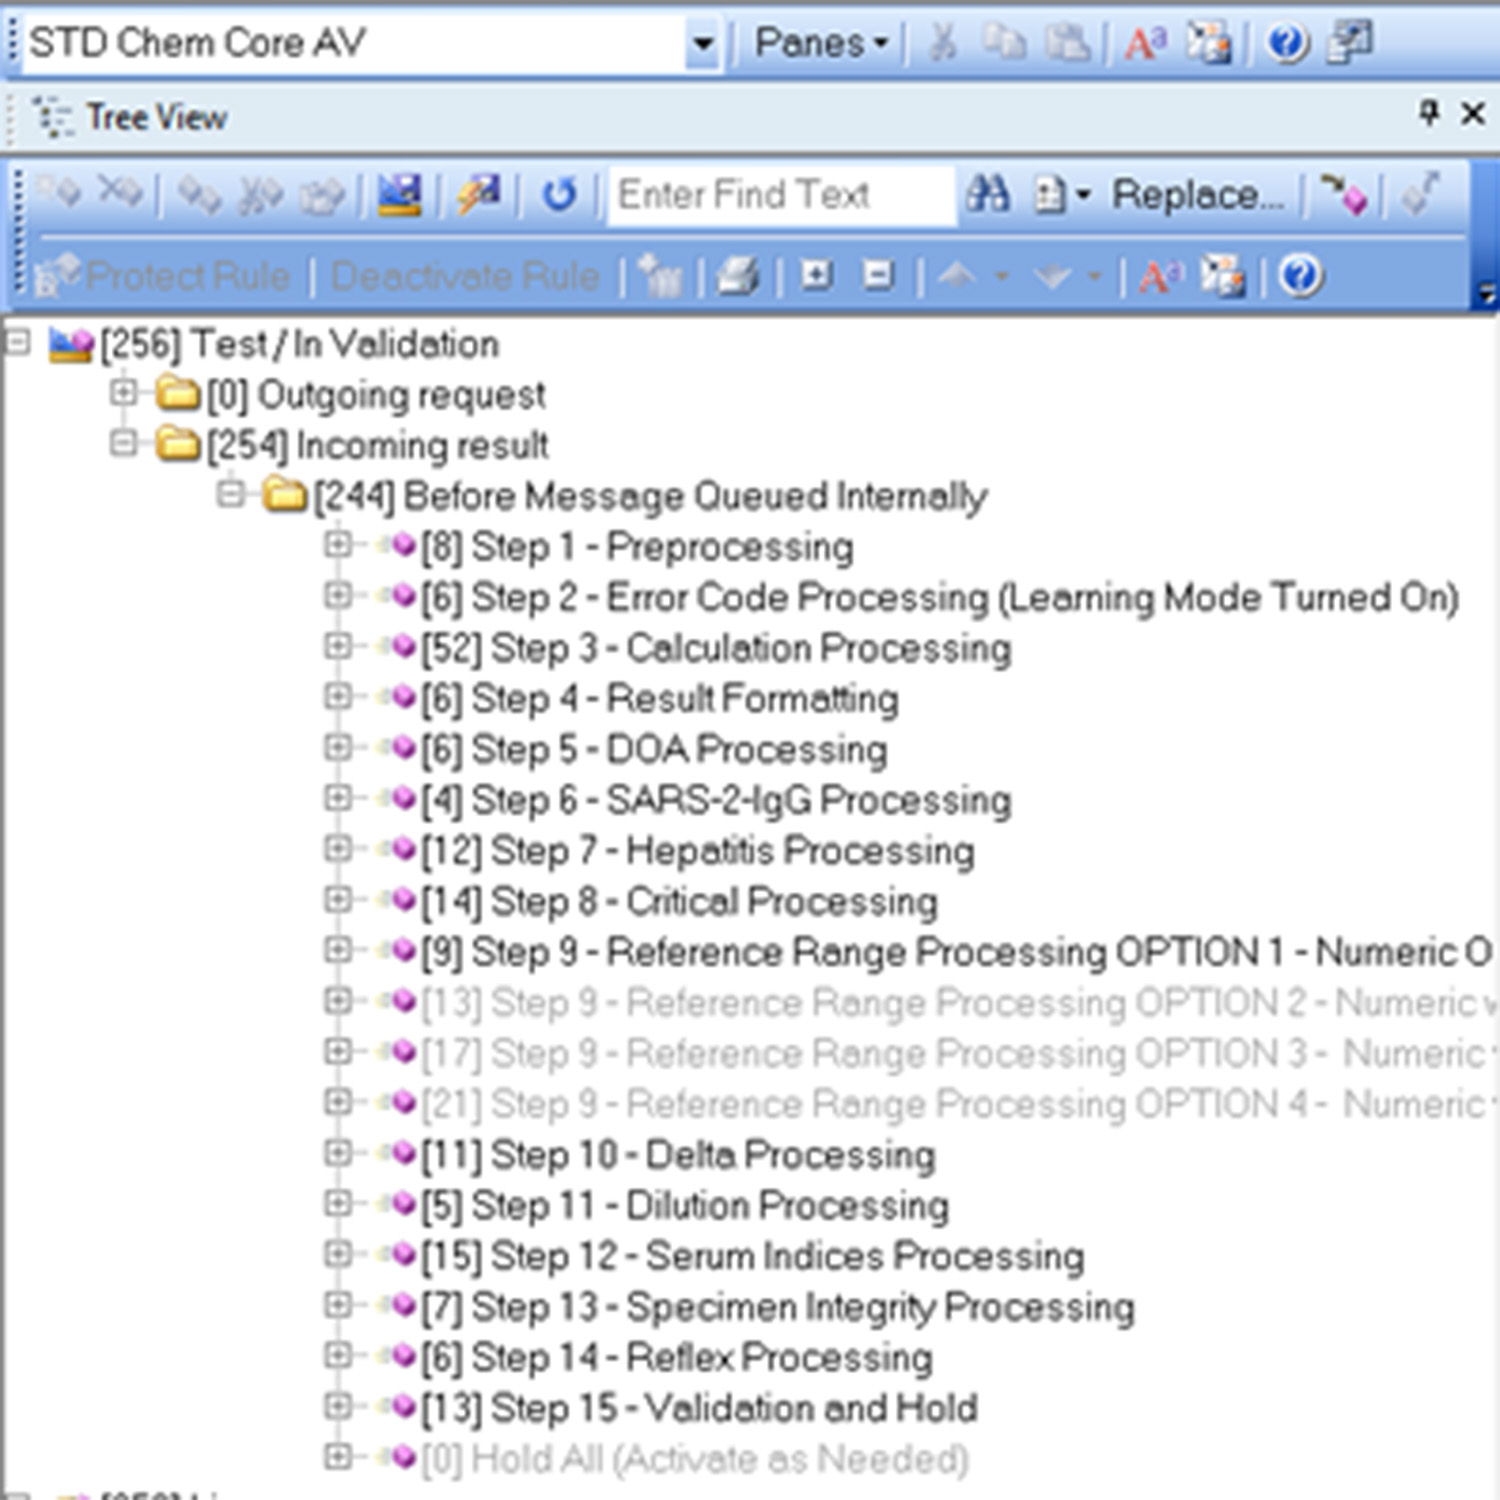

Comprehensive Rules Engine

The IM rules engine supports fully customizable workflows that allow customers to streamline and improve patient care. Rules can range from simple, such as flagging a critical value, to complex – a result triggering a next-step reflex test.

Plus, a built-in testing engine can validate rules before they go into production.